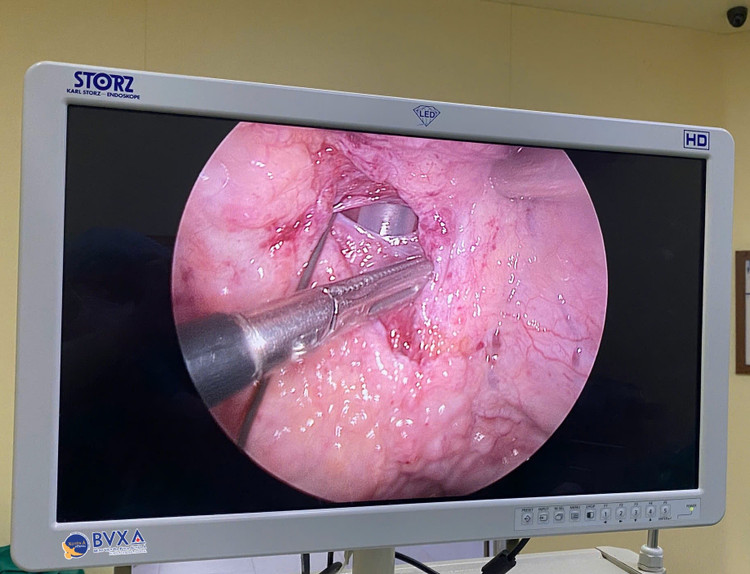

Màn hình tăng sáng cho thấy vỡ bàng quang - Ảnh BVCC

Ngay khi tiếp nhận, các bác sĩ đã thực hiện các xét nghiệm chẩn đoán, chụp CT – scan bụng 160 lát cắt ghi nhận bàng quang căng, nhiều dịch ổ bụng, hai thận ứ nước, xét nghiệm máu lại thấy tình trạng suy thận. Vốn có kinh nghiệm xử trí tình huống tương tự trước đây, nghi ngờ nhiều nhất là tình trạng vỡ bàng quang tự phát trong phúc mạc, các bác sĩ Khoa Ngoại tiết niệu đã chỉ định người bệnh nội soi bàng quang và xử trí cấp cứu ngay.

Kết quả soi ghi nhận niêm mạc bàng quang phù nề, nước tiểu đục, có lỗ thủng nhỏ ở thành sau bàng quang gần đỉnh bàng quang với kích thước 5mm. Đây là một trong những trường hợp vỡ bàng quang trong phúc mạc hiếm gặp được chẩn đoán bằng nội soi bàng quang, khi mà các xét nghiệm chẩn đoán vỡ bàng quang thường quy không phát hiện được.

Trước tình trạng trên, bệnh nhân được chỉ định phẫu thuật nội soi ổ bụng khâu lại bàng quang vỡ. Trong quá trình phẫu thuật, ekip đã hút ra được hơn 1000ml nước tiểu trong ổ bụng”.